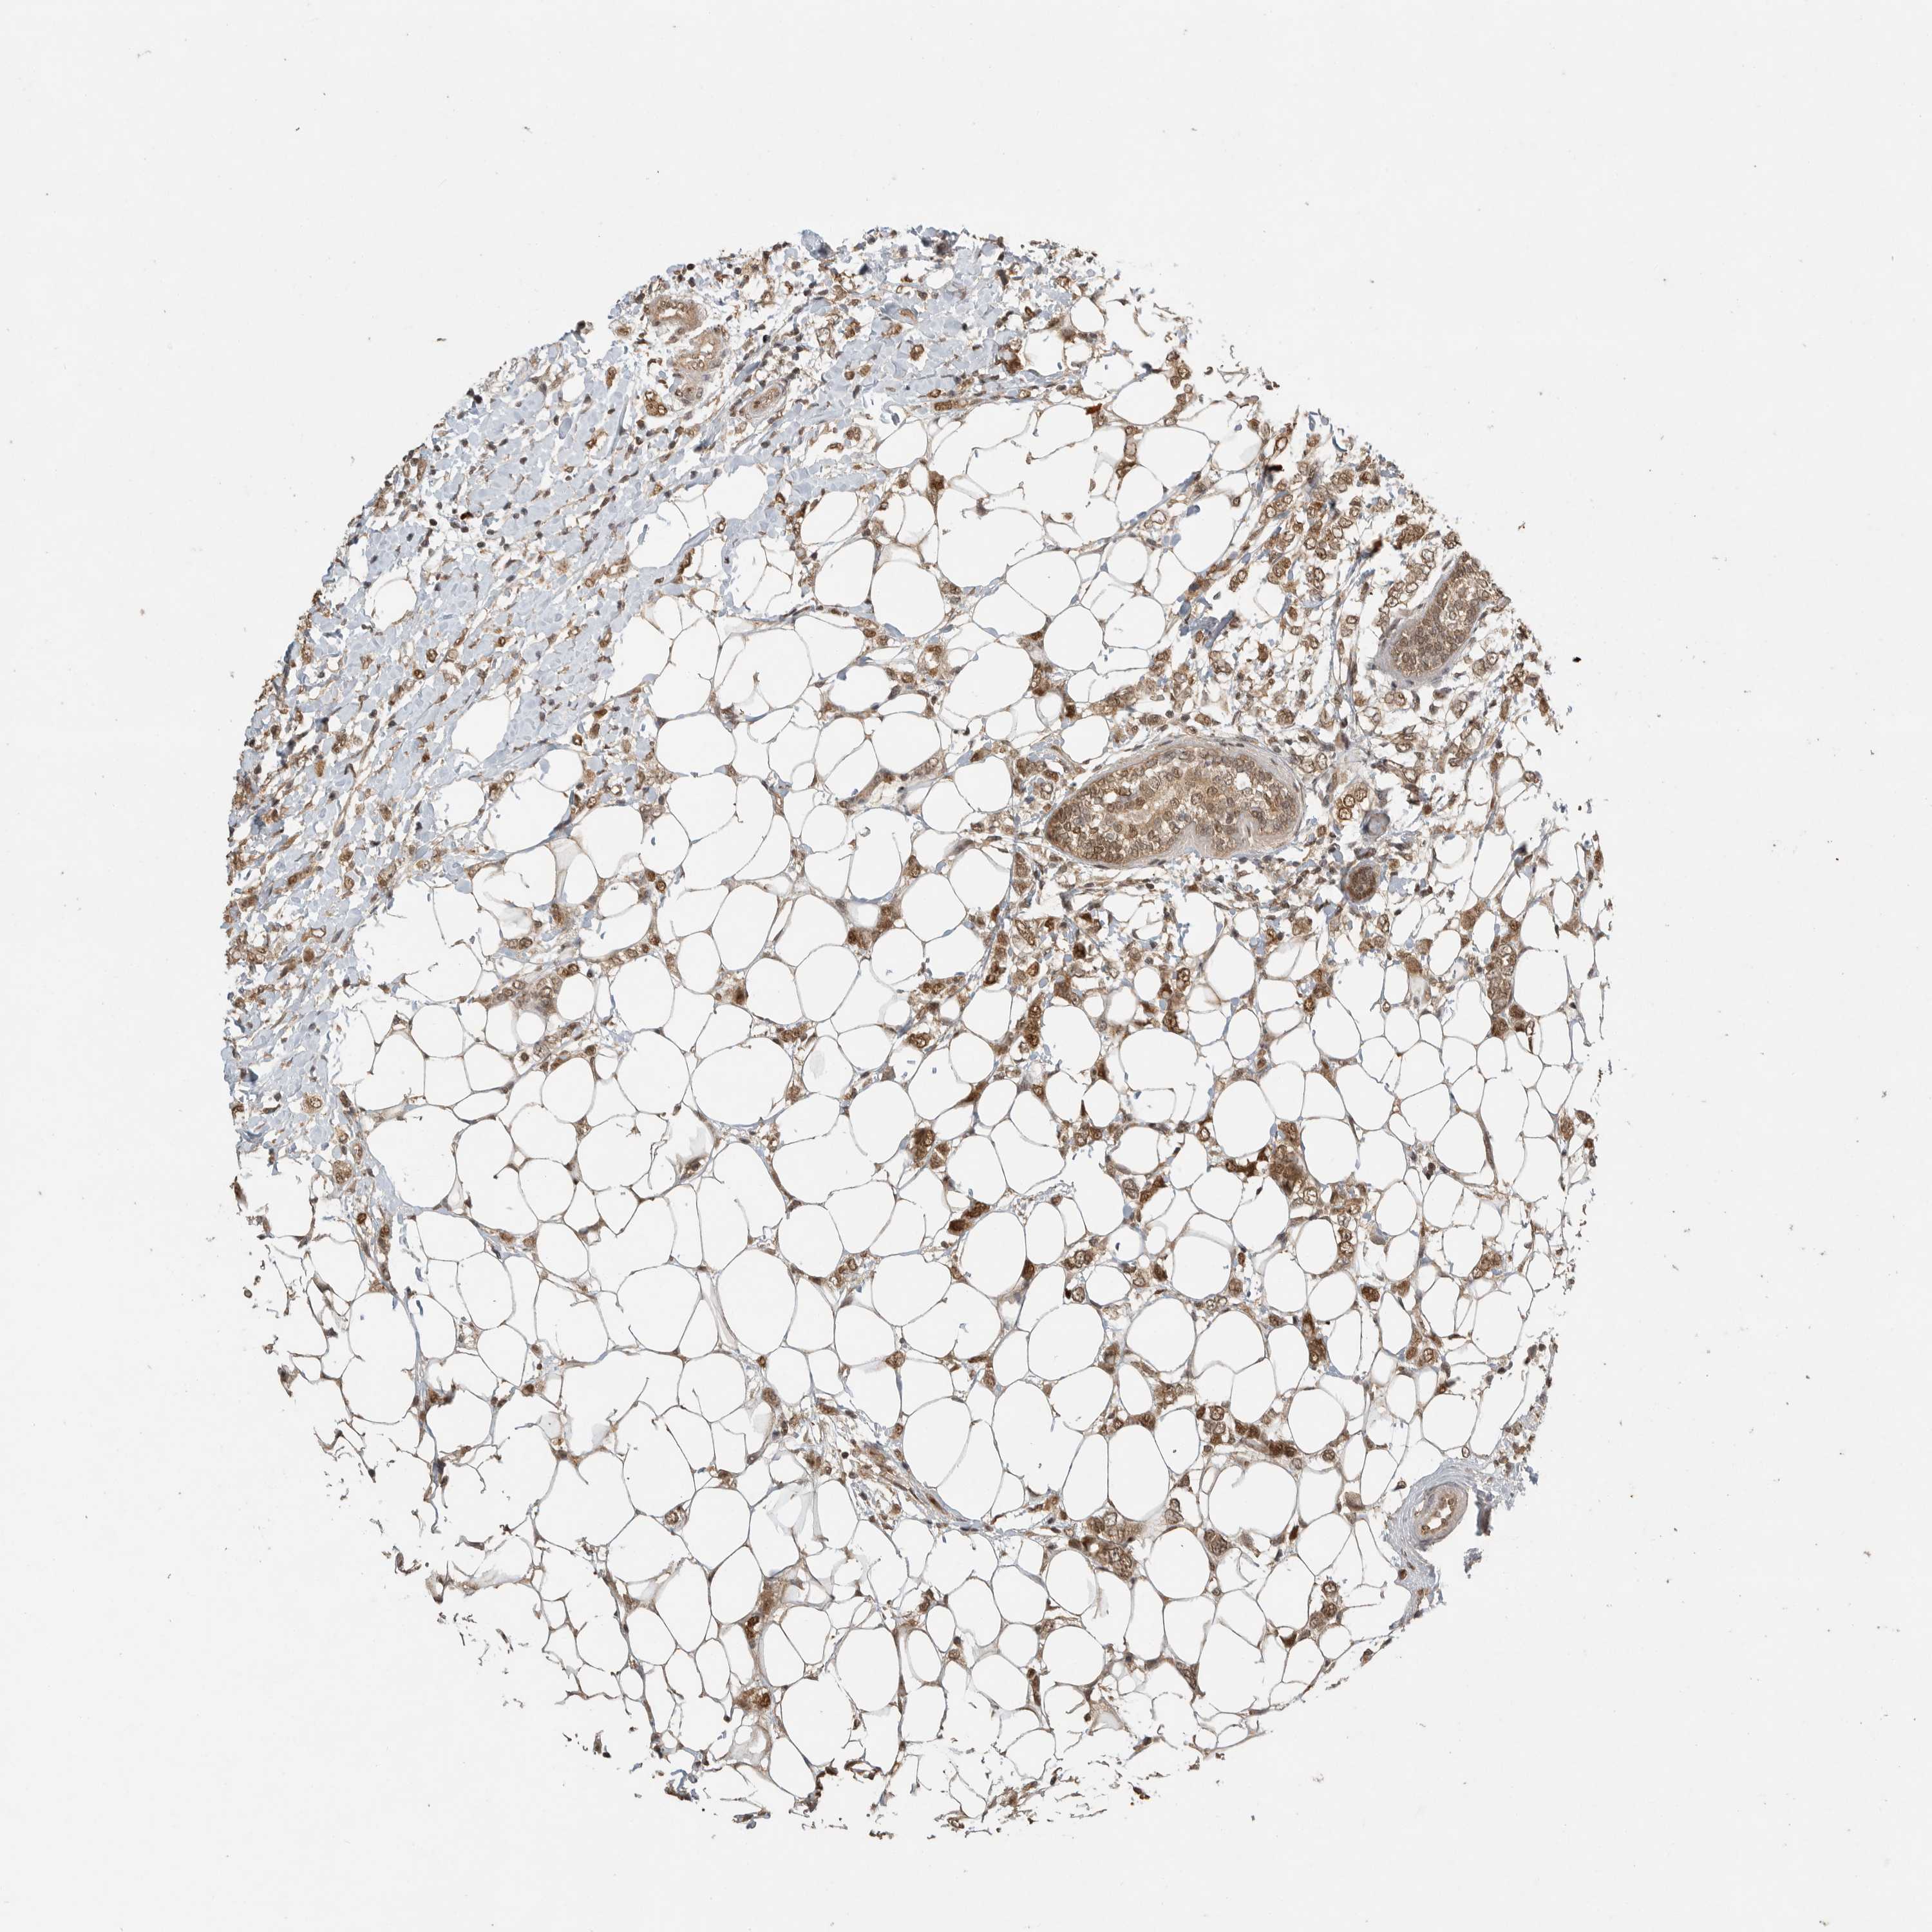

CANCER BREAST CANCER Show tissue menu

BRCA TCGA BRCA VALIDATION PROTEIN EXPRESSION